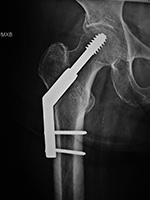

| Dynamic compression hip screw |

Dynamic compression hip screw, partially threaded cannulated cancellous fixation screw and washer |

Dynamic compression hip screw

| There is also a partially threaded cannulated cancellous fixation screw. |